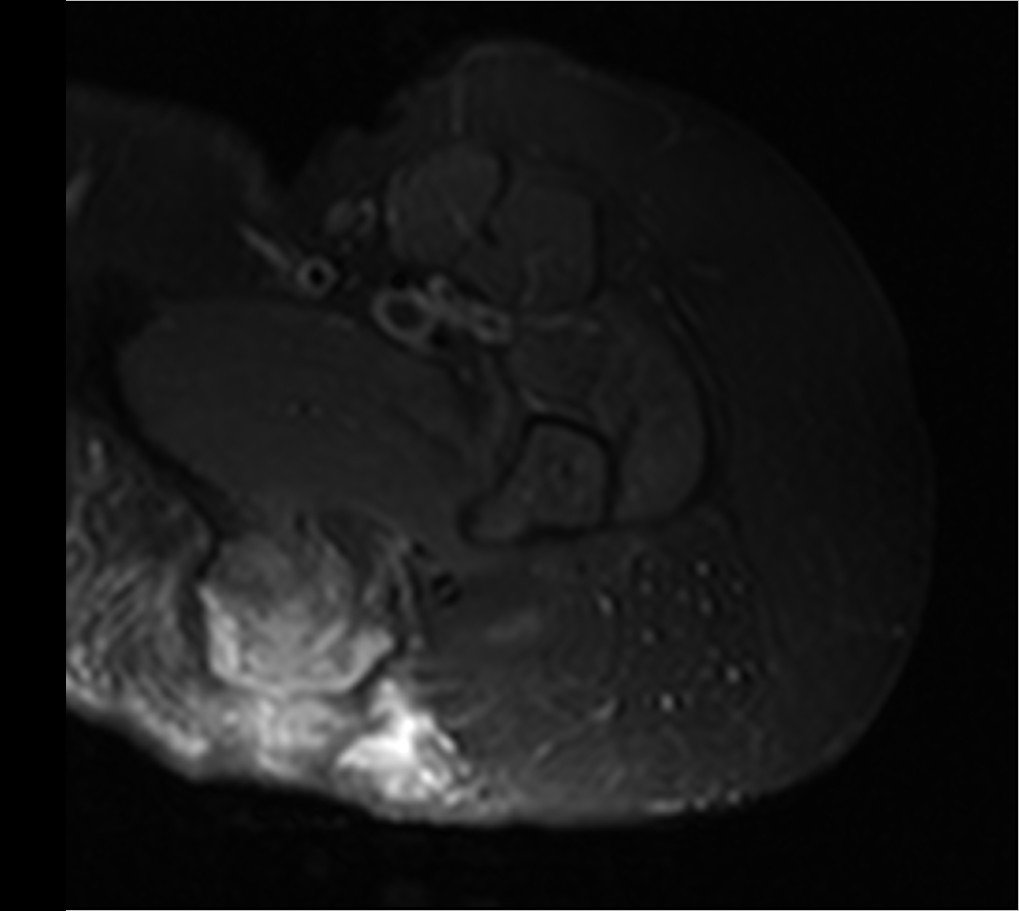

Примеры МРТ-исследования тазобедренного сустава